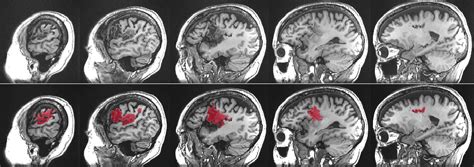

Alright guys, let’s break down aphasia in more detail. So, aphasia isn’t just one single thing; it’s a spectrum of language disorders. The core issue is that the brain’s ability to process language has been disrupted. This usually happens when there’s damage to specific areas of the brain, most commonly the left hemisphere, which is dominant for language in most people. The most frequent culprit behind this damage is a stroke , where blood flow to a part of the brain is interrupted, causing brain cells to die. Other causes can include traumatic brain injuries (like from a car accident or a fall), brain tumors, infections, or even progressive neurological diseases like dementia. The specific type and severity of aphasia depend heavily on the location and extent of the brain damage. It’s crucial to remember that aphasia does not affect a person’s intellect. Someone with aphasia can still think, reason, and feel emotions just as they did before. The difficulty lies purely in the expression and comprehension of language. This is a really important distinction to make because it can be disheartening when people wrongly assume aphasia means a loss of cognitive abilities. The frustration for individuals with aphasia often stems from this very misunderstanding. They might know what they want to say, but the words just won’t come out, or they might struggle to grasp what others are saying, even though their hearing is perfectly fine. It’s like having a word on the tip of your tongue, but it’s permanently stuck there. This can lead to significant emotional distress, isolation, and a feeling of being disconnected from the world. Understanding these nuances is the first step towards providing effective support and fostering an environment where communication, in whatever form it takes, can flourish.

So, how does aphasia actually happen? The main reason, as we touched upon, is damage to the brain’s language areas . Let’s chat about the most common causes. Strokes are the big one, guys. They happen when blood supply to a part of the brain is cut off (ischemic stroke) or when a blood vessel bursts in the brain (hemorrhagic stroke). These events can quickly damage brain cells, and if those cells are involved in language processing, aphasia can result. Think about it: the brain is incredibly complex, with different regions specializing in different tasks. The parts responsible for understanding grammar, retrieving words, forming sentences, and interpreting meaning are all susceptible to stroke damage. Following stroke, it’s common for people to experience aphasia, and the type can vary widely. Another major cause is traumatic brain injury (TBI) . This can result from a blow to the head, a fall, or any incident where the brain experiences sudden, forceful movement. TBIs can cause widespread damage, and if the language centers are hit, aphasia is a likely outcome. This is why proper safety measures, like wearing helmets, are so important! Brain tumors can also lead to aphasia. As a tumor grows, it can press on or invade brain tissue, disrupting normal function. If the tumor is located in or near the language areas, it can impair communication. Similarly, brain infections , such as encephalitis (inflammation of the brain), can cause swelling and damage that affects language abilities. Less commonly, but still a possibility, are progressive neurological conditions . Diseases like Alzheimer’s disease and other forms of dementia can gradually damage brain cells over time, and as the disease progresses, it can impact language skills, leading to various forms of aphasia. It’s also worth noting that aneurysms (weakened spots in blood vessel walls) or arteriovenous malformations (AVMs) (abnormal tangles of blood vessels) in the brain can rupture, leading to bleeding and subsequent aphasia. The key takeaway here is that anything that disrupts the normal functioning of the brain’s language network can potentially lead to aphasia. Understanding these causes helps us appreciate the vulnerability of our brain and the importance of seeking prompt medical attention if any of these events occur.

Now, let’s get into the nitty-gritty of aphasia types. It’s super important to know that aphasia isn’t a single condition; it presents in different forms, each with its own set of challenges. The classification usually depends on which part of the brain is affected and how it impacts both expressive (speaking/writing) and receptive (understanding/reading) language. We’ve got the big players here, and understanding them can really help in recognizing the specific difficulties someone might be facing. First up, we have Broca’s aphasia , often called expressive or non-fluent aphasia. People with this type usually understand language pretty well, but they have a really hard time producing it. Their speech might be slow, effortful, and often consists of short, broken phrases. They might omit small words like ‘the’ or ‘is’, making their sentences sound like telegraphic messages. It’s like they have the words in their head but struggle immensely to get them out. Then there’s Wernicke’s aphasia , also known as receptive or fluent aphasia. This is the flip side. People with Wernicke’s aphasia can speak fluently, but their words often don’t make sense. They might produce long, rambling sentences filled with made-up words (neologisms) or incorrect words (paraphasias). They often have significant difficulty understanding spoken or written language, and they may not even be aware that what they’re saying is nonsensical. It’s a really disorienting experience for them. We also have global aphasia , which is the most severe form. This occurs when there’s extensive damage to the language areas of the brain. Individuals with global aphasia have severe impairments in both speaking and understanding language. Their ability to read and write is also greatly affected. Communication can be extremely limited, making everyday interactions a significant hurdle. Then there are other types, like anomic aphasia , where the main problem is finding the right words. People with anomic aphasia can speak fluently and understand language well, but they struggle with word retrieval, often pausing frequently or using general words like ‘thing’ instead of specific nouns. Conduction aphasia is another interesting one where individuals have difficulty repeating words or sentences, even though their comprehension and spontaneous speech might be relatively intact. Finally, transcortical aphasia includes subtypes (sensory, motor, mixed) that affect specific aspects of language production and comprehension while preserving other abilities, like the capacity to repeat. Recognizing these different types is key for tailoring therapy and support to meet the unique needs of each individual affected by aphasia.